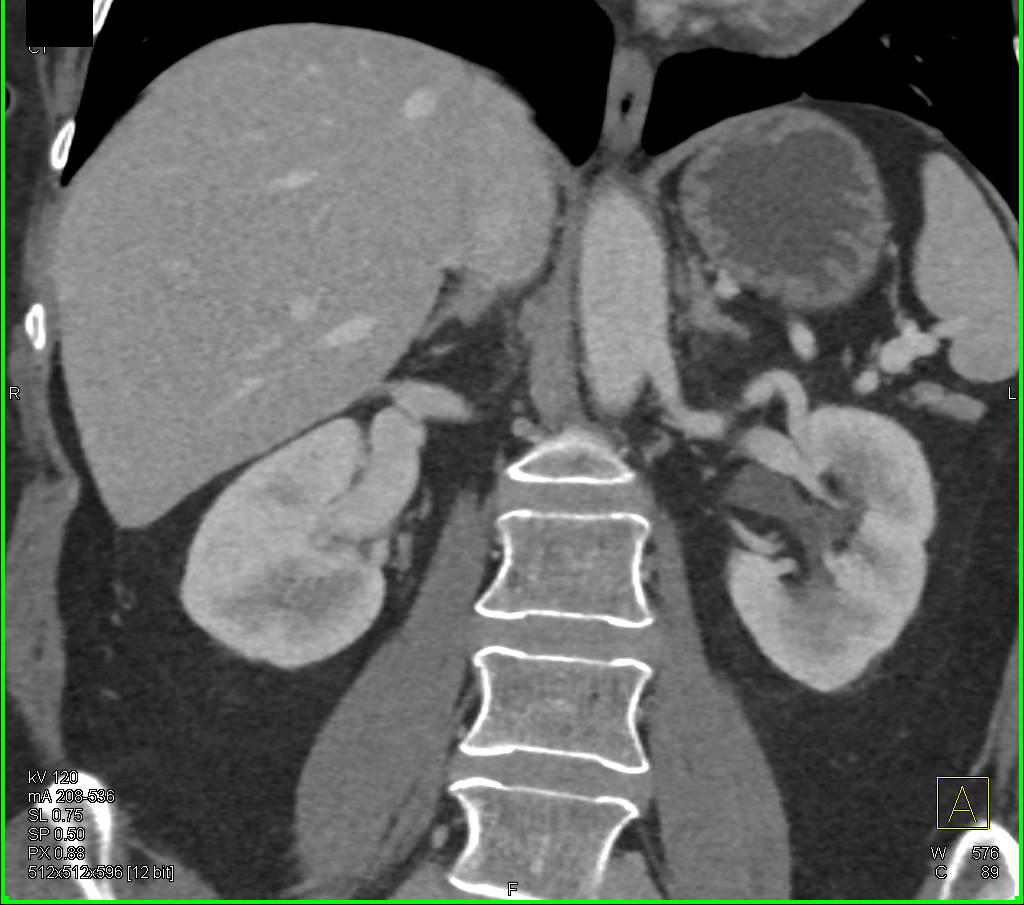

Small Cell Lung Cancer Superior Vena Cava (SVC) Occlusion and Encased Right Pulmonary Artery